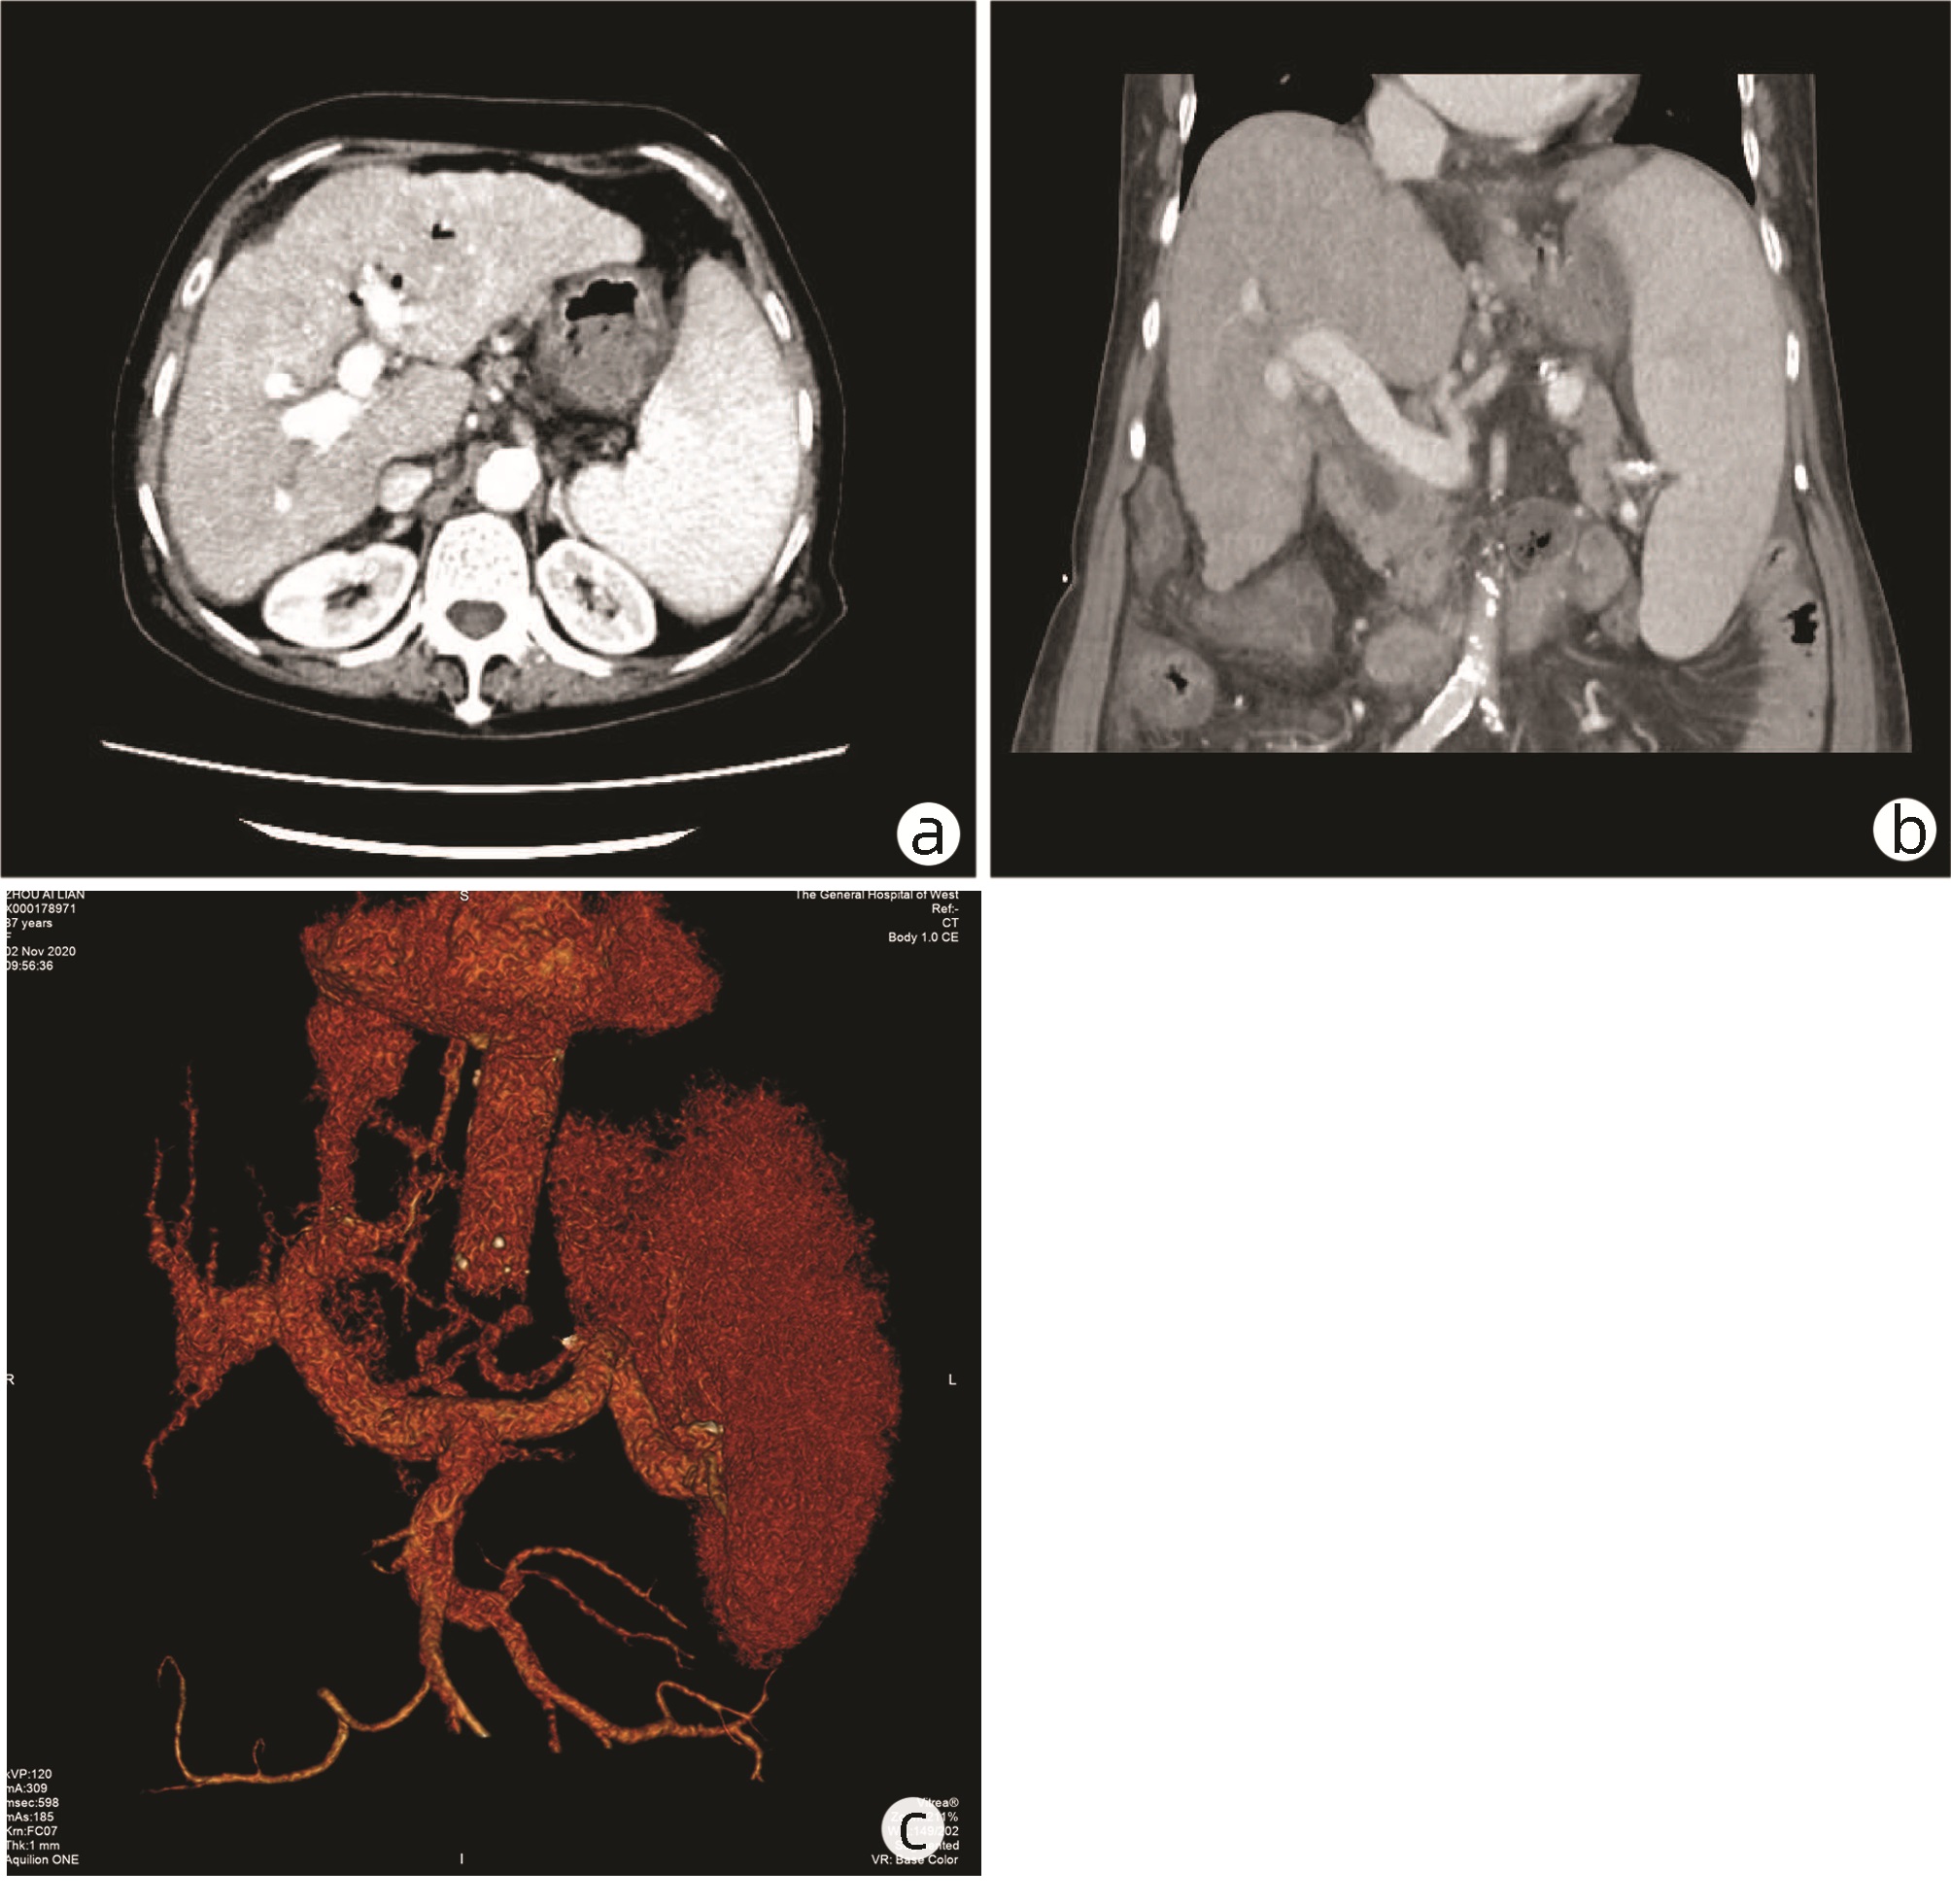

Establishment and application of a preoperative grading system for resectable pancreatic cancer

Chengfang WANG, Zhijiang WANG, Weilin WANG

2022, 38(10): 2325-2333. DOI: 10.3969/j.issn.1001-5256.2022.10.023

Abstract(1021) HTML (589) PDF (2058KB)(81)

Abstract:

Objective  To investigate the risk factors for early recurrence of resectable pancreatic cancer and the establishment and application of a grading system.  Methods  A retrospective case-control study was conducted among 303 patients with resectable pancreatic cancer who underwent radical resection in Department of Hepatobiliary and Pancreatic Surgery, The Second Affiliated Hospital of Zhejiang University School of Medicine, from March 2015 to June 2021, and according to the presence or absence of early recurrence (within 6 months after surgery), the 283 patients directly operated on were divided into early recurrence group with 95 patients and non-early recurrence group with 188 patients; 20 patients who received neoadjuvant therapy before surgery were enrolled as neoadjuvant therapy group. Observation indicators included general information, preoperative imaging data, preoperative laboratory data, routine blood test/blood biochemistry and derived indicators, tumor markers, and coagulation markers, and follow-up was conducted to observe recurrence-free survival. The t-test was used for comparison of normally distributed continuous data between two groups, and the Mann-Whitney U test was used for comparison of non-normally distributed continuous data between two groups; the chi-square test was used for comparison of categorical data between two groups. A multivariate Logistic regression analysis was used to investigate the risk factors for early recurrence in patients with pancreatic cancer, and the receiver operating characteristic (ROC) curve was used to determine the optimal cut-off value of each indicator. The Kaplan-Meier curve was plotted, and the Log-rank test was used for comparison of recurrence-free survival time between groups.  Results  The univariate analysis showed that compared with the non-early recurrence group, the early recurrence group had significantly lower body mass index (BMI) and triglyceride and significantly higher CA19-9, CA242, CA125, and plasma fibrinogen (all P < 0.05). The multivariate logistic regression analysis showed that BMI (odds ratio [OR]=1.150, 95% confidence interval [CI]: 1.038-1.273, P=0.007), plasma fibrinogen (OR=2.513, 95%CI: 1.355-4.663, P=0.003), and CA242 (OR=2.482, 95%CI: 1.067-5.774, P=0.035) were independent risk factors for early recurrence in patients with resectable pancreatic cancer. BMI, CA242, and plasma fibrinogen were included in the grading system, with a cut-off value of 23.00 kg/m2, 30.0 U/mL, and 4.00 g/L, respectively. BMI < 23.00 kg/m2 was counted as 1 point, otherwise it was counted as 0 point; CA242≥30.00 U/mL was counted as 1 point, otherwise it was counted as 0 point; plasma fibrinogen ≥4.00 g/L was counted as 1 point, otherwise it was counted as 0 point; the total score was 0-3 points. The patients in both the early recurrence group and the non-early recurrence group were scored, and the results showed that the early recurrence group had a significantly higher score than the non-early recurrence group [2(0-3) points vs 1(0-3) point, Z=-5.339, P < 0.001]. The Kaplan-Meier curve analysis showed that there was a significant difference in time to recurrence between groups (χ2=28.116, P < 0.001), and the higher the score, the shorter the expected time to recurrence. The patients with 3 points were defined as high-risk group and those with 0-2 points were defined as low-risk group, and the early recurrence rate was 84.6% in the high-risk group and 31.2% in the low-risk group.  Conclusion  The grading system based on BMI, plasma fibrinogen, and CA242 can reliably predict postoperative recurrence.